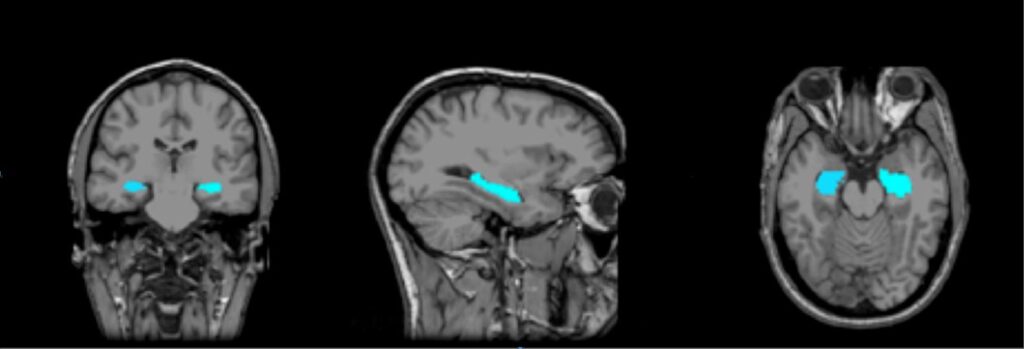

Գիտնականները դեռևս ամբողջությամբ չեն հասկանում SDAM-ի պատճառները, բայց հիմնական «կասկածյալը» հիպոկամպն է՝ ուղեղի այն հատվածը, որը պատասխանատու է հիշողությունների ձևավորման և պահպանման համար։ Ուսումնասիրությունները ցույց են տվել, որ SDAM ունեցող մարդկանց մոտ հիպոկամպը կարող է լինել մի փոքր ավելի փոքր կամ պակաս ակտիվ, քան միջին վիճակագրական մարդու մոտ։